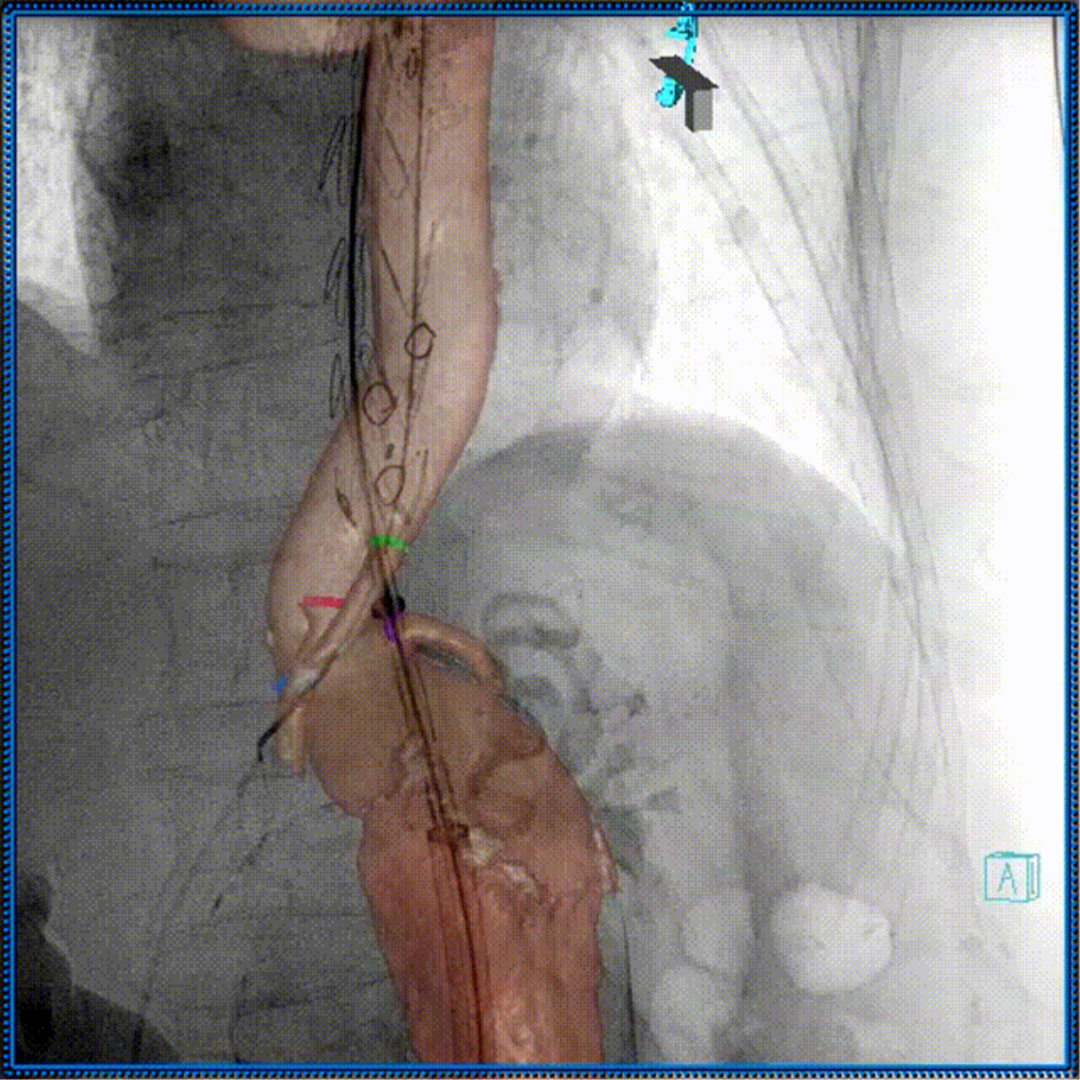

术中3D影像引导,主体支架精准定位

3D影像引导下,

主体支架窗口与弓上三分支开口对位

依次超选无名、左颈总及左锁骨下动脉

术后造影,支架形态良好,分支血流通畅